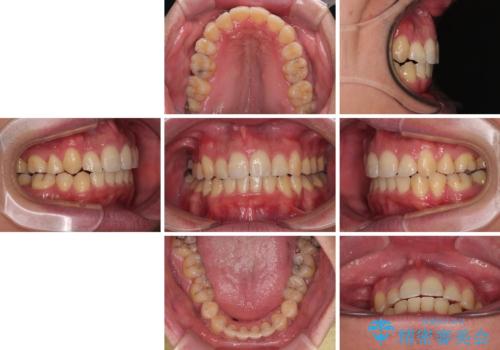

狭くて前方に飛び出した歯列 拡大装置を併用したワイヤー抜歯矯正治療

上下前歯の前後差が非常に大きく、3年以上の治療期間が予想されましたが、無事に3年間ちょうどで仕上げることができました。